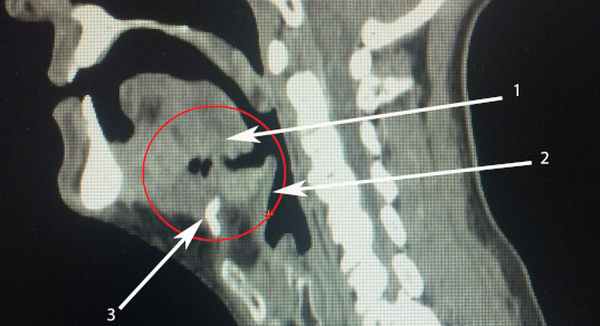

• Лучший диагностический критерий:

о Внутреннее ларингоцеле: тонкостенная заполненная воздухом или жидкостью кистозная полость, сообщающаяся с желудочком гортани

о Смешанное ларингоцеле: внутреннее ларингоцеле + распространение через щитоподъязычную мембрану за пределы гортани

о Пиоларингоцеле: ларингоцеле, заполненное гноем, с толстыми накапливающими контраст стенками

о Вторичное ларингоцеле: патология голосовых складок или нижней части преддверия гортани

(Слева) На схеме фронтального среза гортани показано ларингоцеле, распространяющееся за пределы гортани. У этого образования можно выделить перешеек, т.е. область, где ларингоцеле проникает через щитоподъязычную мембрану в нижнее подчелюстное пространство. Обратите внимание на стенозирование просвета гортанного желудочка.

(Справа) Аналогичное образование представлено на фронтальном КТ-срезе с КУ. Это т.н. «смешанное» ларингоцеле - оно состоит из внутренней (внутригортанной) и наружной (внегортанной) порций. Полость ларингоцеле прослеживается до гортанного желудочка. (Слева) Аксиальная КТ с КУ, типичные признаки жидкостного внутреннего (простого) ларингоцеле. Наблюдается не накапливающее контраст образование жидкостной плотности, ограниченное околоскладочной областью преддверия гортани латеральней ложной голосовой складки.

(Справа) На аксиальном КТ-срезе с КУ профессионального трубача показана заполненная воздухом полость, ограниченная правой околоскладочной областью. Это типичные признаки воздушного внутреннего (простого) ларингоцеле.